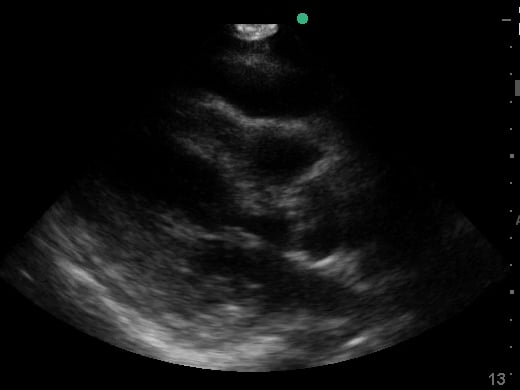

Pericardial effusion in cardiac ultrasound refers to an abnormal accumulation of fluid within the pericardial sac, the double-layered membrane surrounding the heart. This condition can impede the heart’s ability to fill and pump blood effectively, potentially leading to cardiac tamponade, a life-threatening emergency. Early detection through echocardiography is crucial for timely medical intervention and improved patient outcomes.

Utilizing medical ultrasound, healthcare professionals can accurately identify and quantify pericardial effusions, assessing their size, location, and hemodynamic impact. Ultrasound imaging provides real-time visualization of the fluid build-up, enabling precise diagnosis and guiding potential therapeutic procedures such as pericardiocentesis. This non-invasive technique is indispensable for managing cardiac health and preventing severe complications.